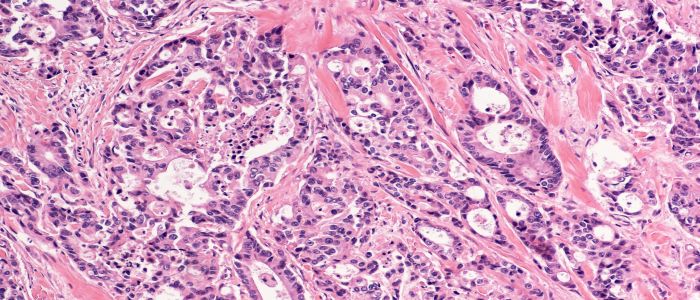

Glasgow team will transform bowel cancer screening into a precision medicine tool using AI

UofG awarded £38m to deliver game-changing Precision Medicine project